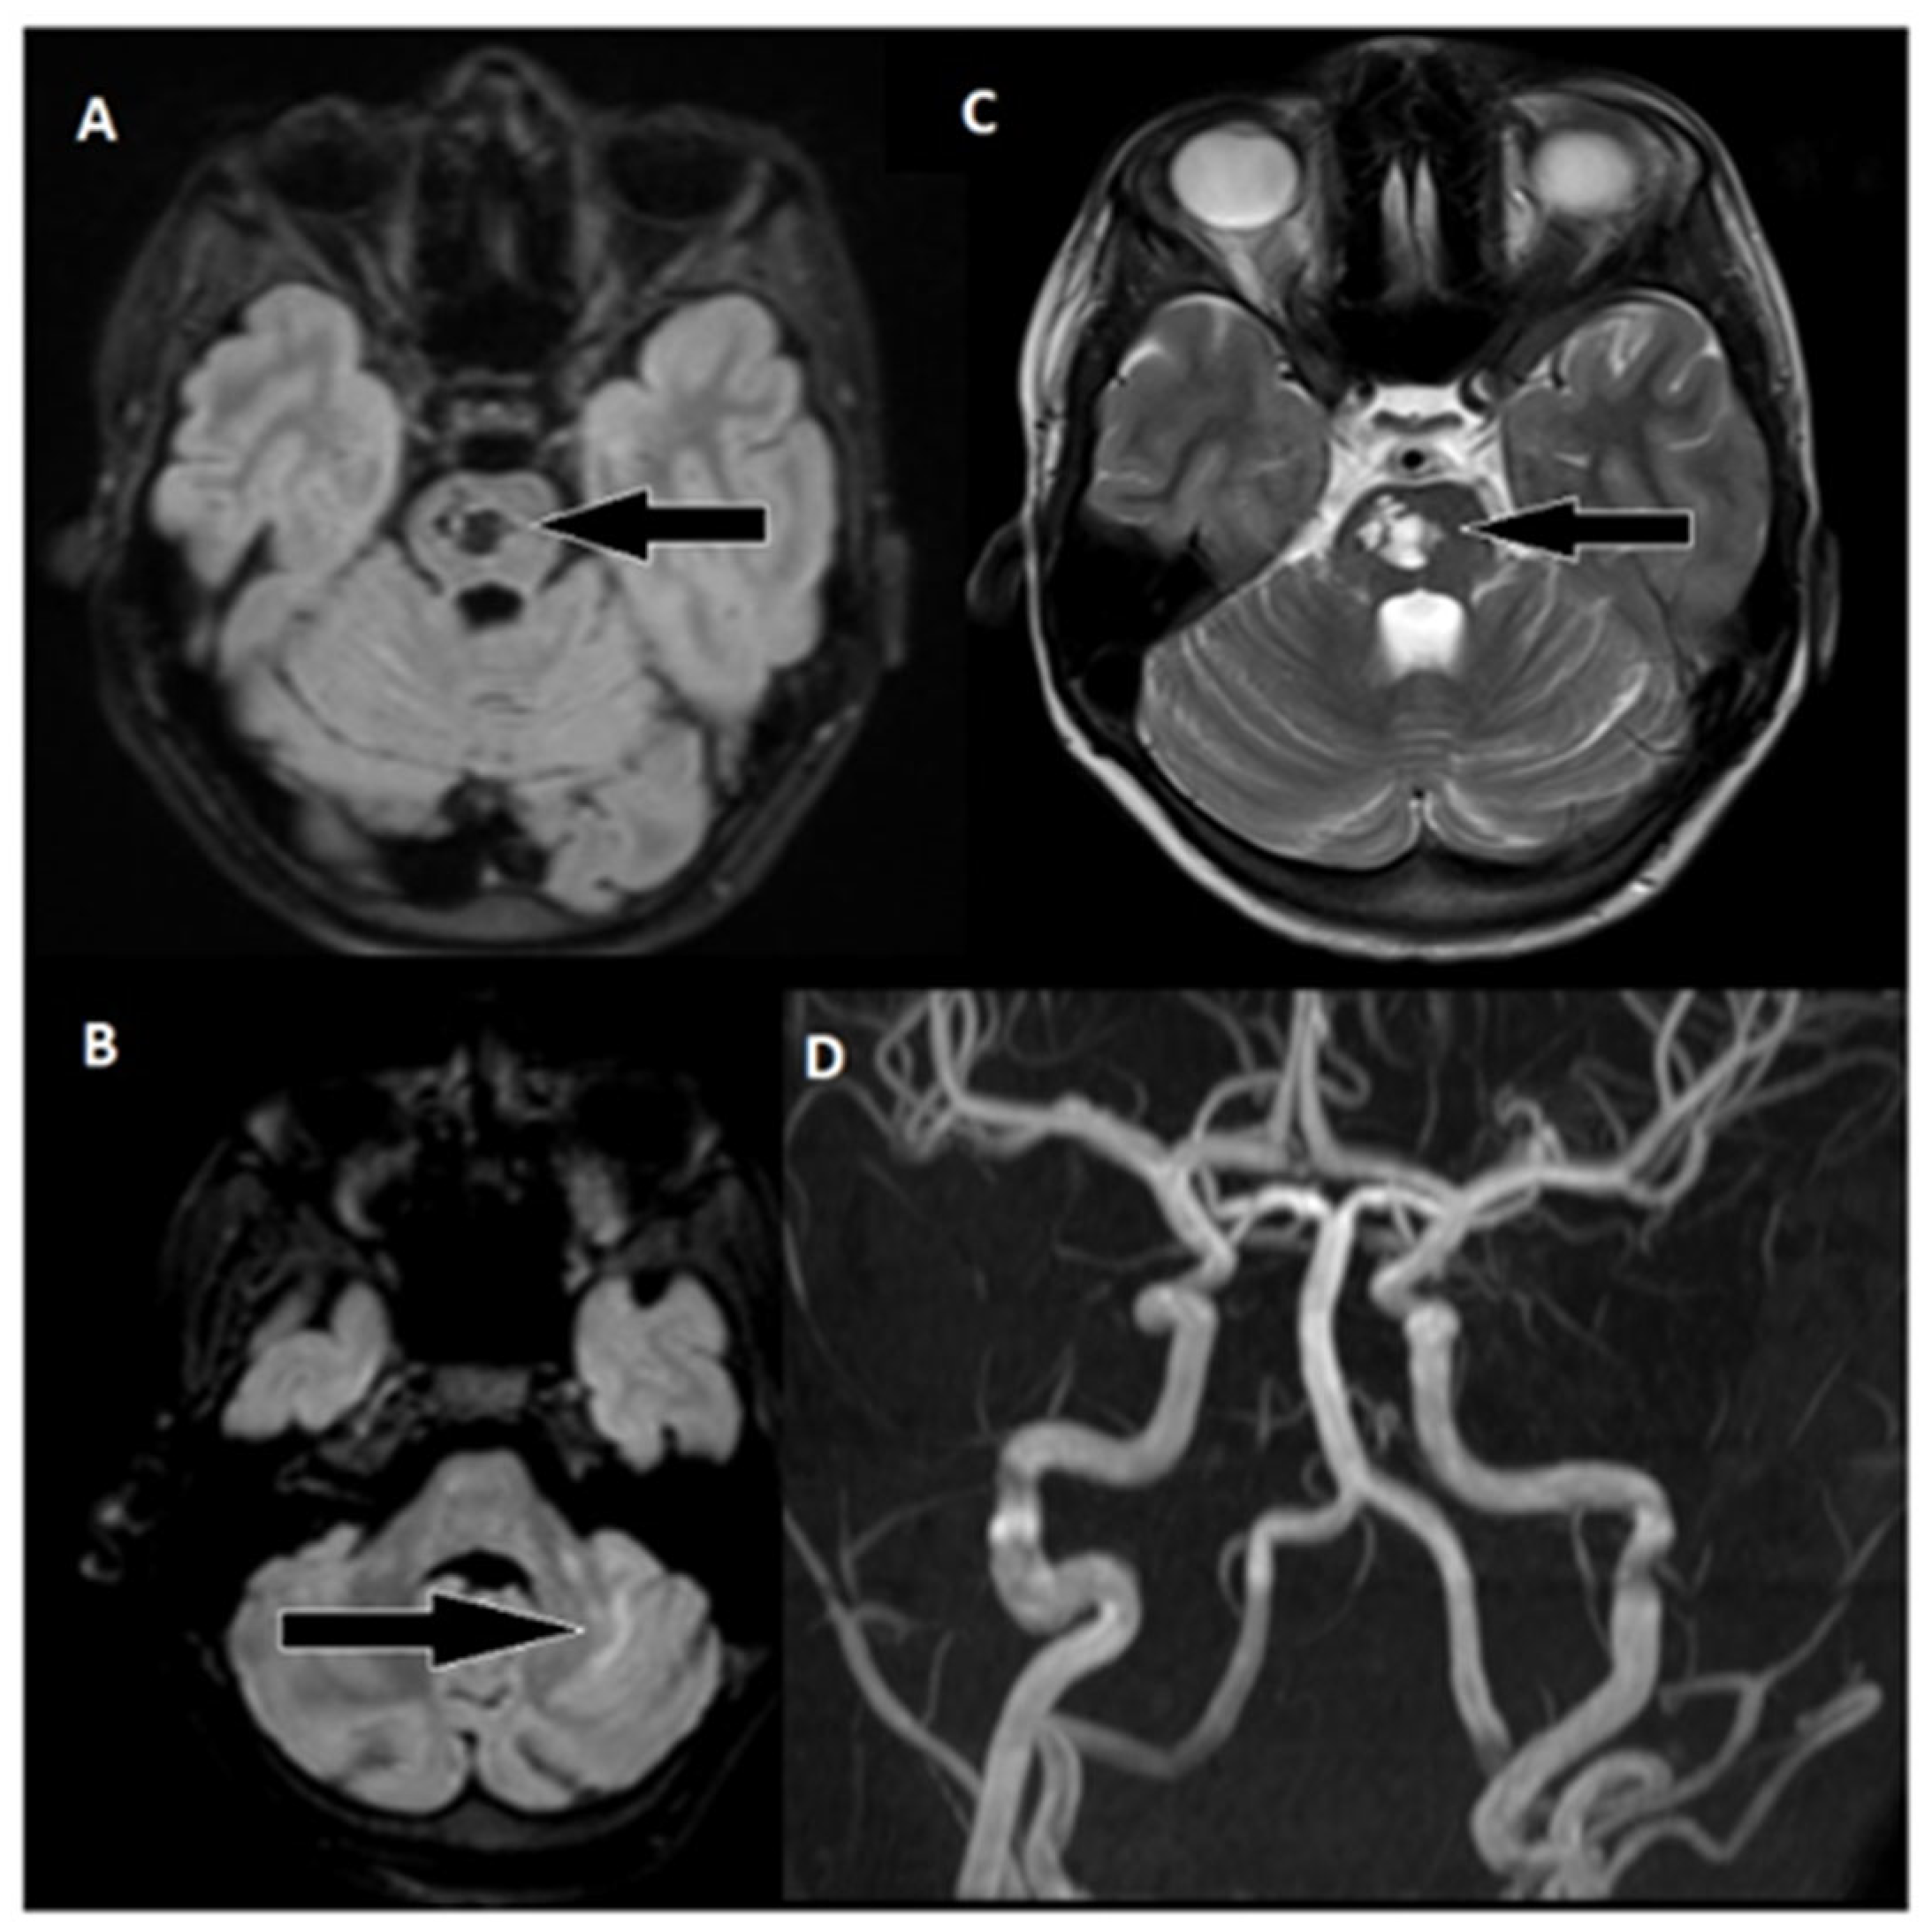

Figure 5. Follow-up MRI of the brain approximately 6 months after thrombectomy. (A) Markedly hypointense areas on the right side of the pons in the FLAIR sequence, indicating scarring. Corresponding hyperintense changes are observed on: (C) T2 weighted images, with a distinct hyperintense area on the right side of the pons (arrow). (B) Changes in the upper part of the left cerebellar hemisphere are visible in the FLAIR sequence. (D) An MRA examination shows unobstructed flow in the basilar artery and both cerebral posterior arteries.

During the six-month follow-up, the patient exhibited a complete neurological recovery, as evidenced by an NIHSS score of 0 and an mRS score of 0. An MRI scan conducted at this time revealed scarring with hypointense areas on the right pons in the FLAIR sequence. Importantly, magnetic resonance angiography (MRA) confirmed unobstructed flow in the basilar artery. This positive outcome marked a significant milestone in the patient's journey toward recovery and underlined the remarkable resilience of the young patient in overcoming the challenges posed by this enigmatic stroke.